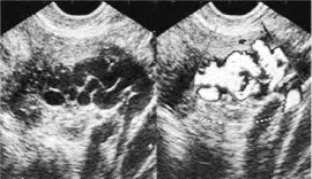

4.CDFI显示盆腔静脉丛呈红、蓝镶嵌的血流信号,纡曲走行,严重者子宫肌壁间纡曲的静脉网,血流速较低。CDFI对该病诊断意义较大(图33-18)。

图33-18 盆腔静脉曲张症二维与彩色多普勒超声像图(见彩图46)

血流呈网状分布